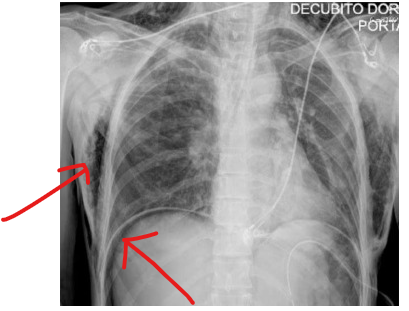

在支气管镜操作室内行胸部X线检查,显示弥漫性肺气肿及气腹(图1)。